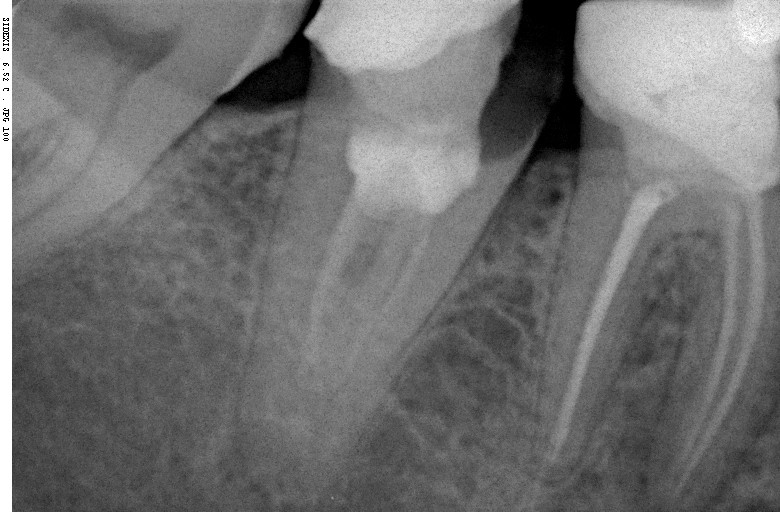

Прицельный радиовизиографический снимок можно сделать в любой из наших клиник. В отличие от обычных прицельных рентгенограмм зубов, доза лучевой нагрузки при проведении подобного исследования в несколько раз ниже, поэтому таких снимков можно сделать очень много. Например, по существующим стандартам, терапевт стоматолог может сделать до десяти снимком зуба в процессе эндодонтического лечения — и это, разумеется, необходимо для качественного лечения каналов зубов.

В хирургической практике я использую прицельные снимки как для первичной диагностики: например, чтобы быстро понять локализацию ретинированного зуба мудрости и его отношение к окружающим структурам, либо для интра- и послеоперационного контроля результатов имплантологического лечения. А наличие цифровой базы радиовизиографических снимков позволяет понять, как ведет себя протез на импланте в течение длительного времени: